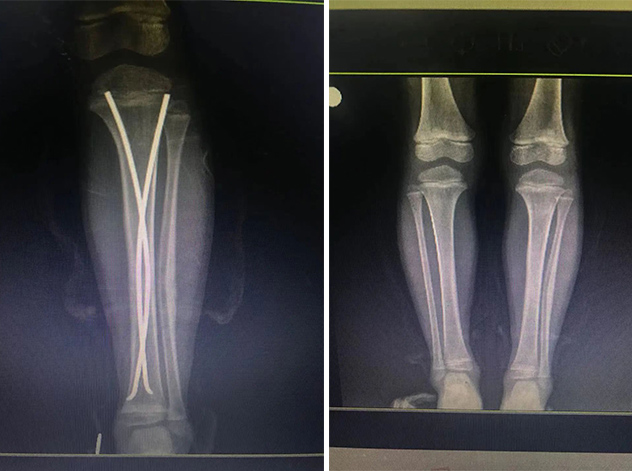

在接下來的康復過程中,睿睿非常配合,恢復的非常好。今年4月12日,睿睿拆除了左腿里的彈性釘。

拆前拆后對比